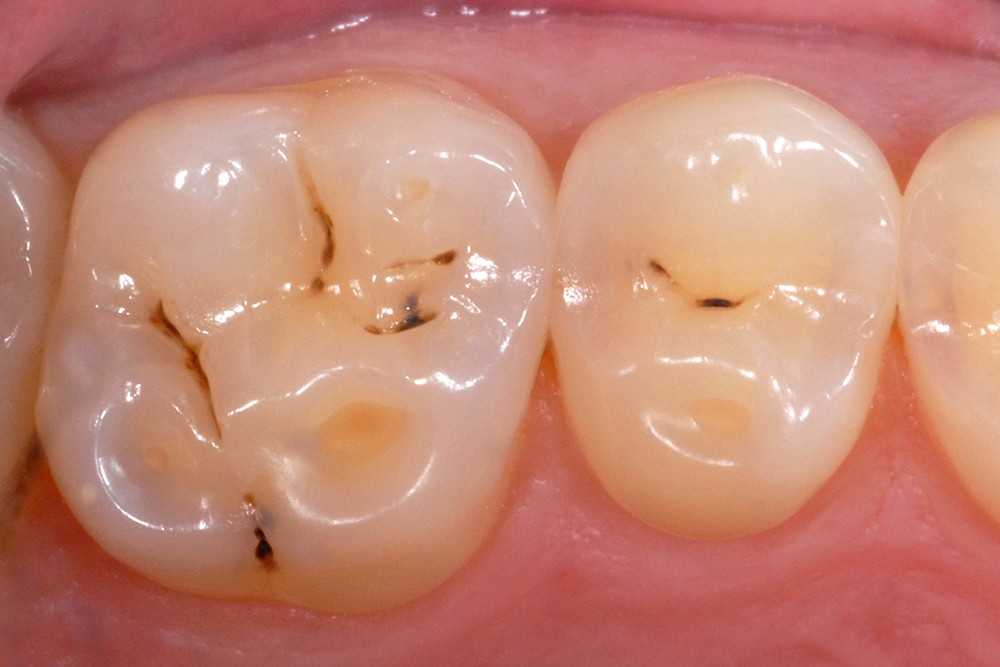

L’érosion survient lorsqu’une attaque chimique (solution acide, chélatant) rompt les liaisons intermoléculaires des tissus dentaires, potentialisant les différents autres modes d’usure mécanique (attrition, abrasion, abfraction) (fig. 5). L’aspect clinique des lésions érosives est polymorphe, mais, d’une manière générale, les surfaces sont lisses, en forme de cupules sur les sommets cuspidiens (fig. 6), de couleur satinée à terne. Les restaurations non affectées par l’environnement corrosif (amalgames, composites, alliages métalliques) surplombent généralement les surfaces amélaires et dentinaires adjacentes, alors que la morphologie dentaire est affectée. Les faces vestibulaires (fig. 7) et palatines (fig. 8) peuvent également présenter des lésions plus ou moins importantes, selon l’origine et le temps d’application de la source acide qui peut être d’origine extrinsèque (sodas, aliments acides) ou intrinsèque (sucs gastriques).